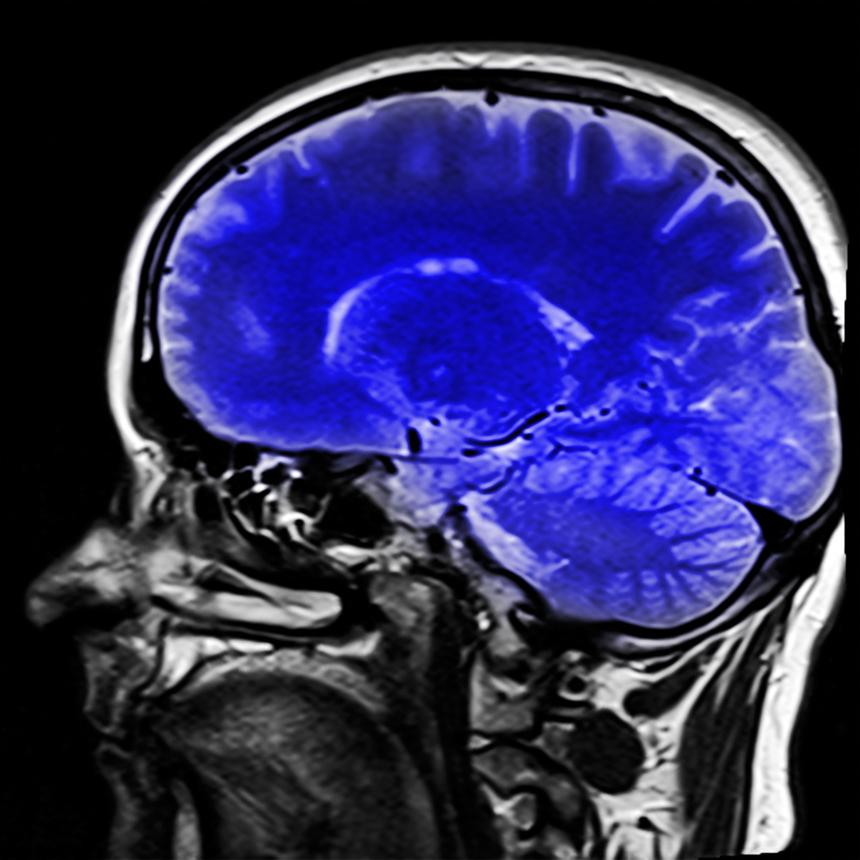

Исследователи изучили более 1200 МРТ-сканов мозга пациентов с расстройством поведения во сне (RBD) и выявили характерные изменения, которые могут предсказать наступление тяжёлых нейродегенеративных заболеваний. У людей с RBD отсутствует обычный паралич мышц во время сна, что приводит к агрессивным движениям или вокализации, вызванным сновидениями.

Такое поведение часто встречается у людей старше 50 лет, причём у 90% из них в конечном итоге диагностируется болезнь Паркинсона или деменция с тельцами Леви. С помощью искусственного интеллекта были выявлены два типа атрофии мозга, что помогло предсказать болезнь на ранних стадиях и, возможно, принять профилактические меры до проявления симптомов. Исследование подчёркивает важность раннего выявления RBD и понимания изменений в мозге для разработки более эффективных стратегий лечения и замедления прогрессирования болезней.